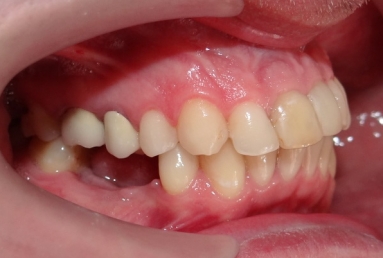

The orthodontic treatment was necessary as the upper maxillary developed assimetricaly, also the teeth were malpositioned. The purpose of the partial braces was to help the final prosthetic treatment, which consisted of two full ceramic crowns for the central incisors, that had root canal treatments, and a ceramic veneer for the lateral incisor, that had a large composite filling. Gingivectomies were also necessary for the right canine and incisors in order to correct the assymetrical gummy smile.